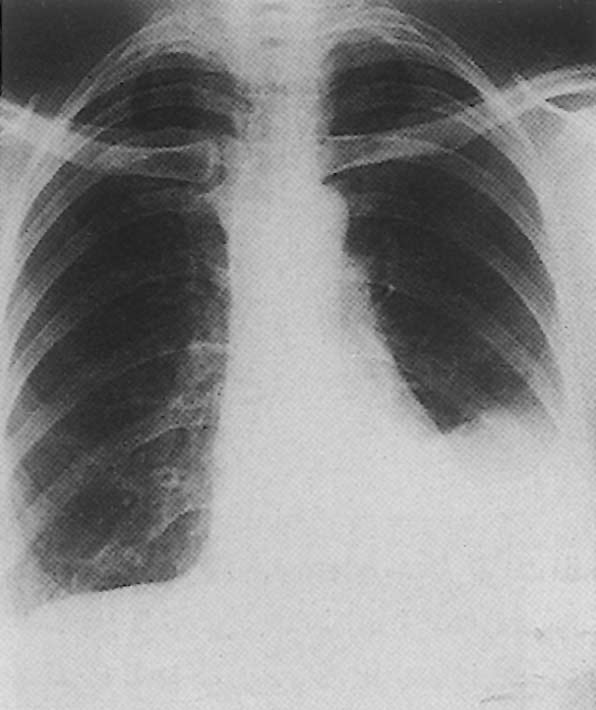

انصباب جنب أيسر

ظهر في سياق مرض شبه نزلي لدى امرأة شابة